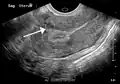

A very large (9 cm) fibroid of the uterus which is causing pelvic congestion syndrome as seen on CT -

A very large (9 cm) fibroid of the uterus which is causing pelvic congestion syndrome as seen on ultrasound -

A small uterine fibroid seen within the wall of the myometrium on a cross-sectional ultrasound view -